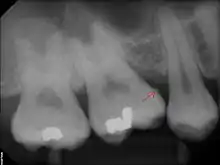

The processes of calculus formation from dental plaque are not well understood. Supragingival calculus formation is most abundant on the buccal (cheek) surfaces of the maxillary (upper jaw) molars and on the lingual (tongue) surfaces of the mandibular (lower jaw) incisors.[15] These areas experience high salivary flow because of their proximity to the parotid and sublingual salivary glands. Subgingival calculus forms below the gumline and is typically darkened in color by the presence of black-pigmented bacteria,[15] whose cells are coated in a layer of iron obtained from heme during gingival bleeding.[16] Dental calculus typically forms in incremental layers[17] that are easily visible using both electron microscopy and light microscopy.[9] These layers form during periodic calcification events of the dental plaque,[15] but the timing and triggers of these events are poorly understood. The formation of calculus varies widely among individuals and at different locations within the mouth. Many variables have been identified that influence the formation of dental calculus, including age, gender, ethnic background, diet, location in the oral cavity, oral hygiene, bacterial plaque composition, host genetics, access to professional dental care, physical disabilities, systemic diseases, tobacco use, and drugs and medications.[15]

Sub-gingival calculus is composed almost entirely of two components: fossilized anaerobic bacteria whose biological composition has been replaced by calcium phosphate salts, and calcium phosphate salts that have joined the fossilized bacteria in calculus formations.[37][38] The initial attachment mechanism and the development of mature calculus formations are based on electrical charge.[39] Unlike calcium phosphate, the primary component of teeth, calcium phosphate salts exist as electrically unstable ions. The following minerals are detectable in calculus by X-ray diffraction: brushite (CaHPO4 · 2 H2O), octacalcium phosphate (Ca8H2(PO4)6 · 5 H2O), magnesium-containing whitlockite (Ca9(Mg,Fe)(PO4)6(PO3OH)), and carbonate-containing hydroxyapatite (approximately Ca5(PO4)3OH but containing some carbonate).[40]